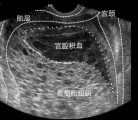

孕早期见红有哪些原因你知道吗?